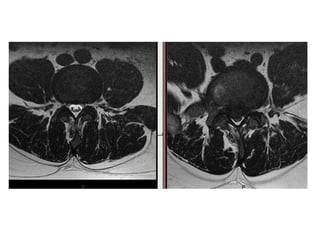

Lumbar MRI (sagittal view)

Lumbar MRI (axial view)